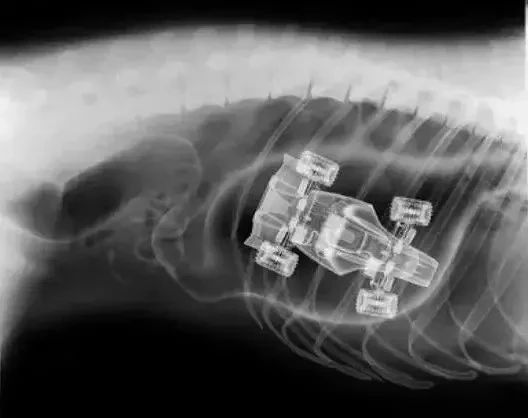

特想知道这个玩具小汽车是怎么开进它肚子的!